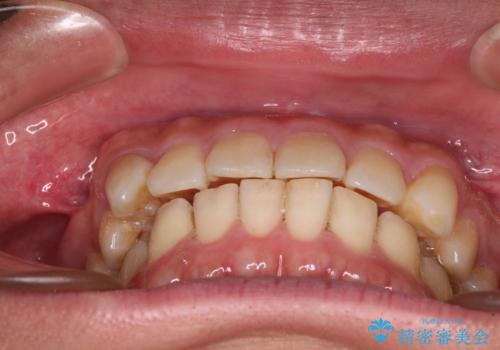

配属異動や長時間勤務などによりインビザラインが十分に装着できない期間があり、インビザライン有効期限5年間ギリギリとなってしまいました。